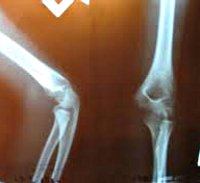

Рентгенография локтевого сустава

Рентгенограмма локтевого сустава в травматологии показана при подозрении на переломы околосуставного и внутрисуставного суставов и переломы плечевой, лучевой и локтевой костей. В других областях медицины этот метод используется для диагностики дегенеративно-дистрофических изменений, новообразований, аномалий развития и гнойных воспалительных процессов. Исследование обычно проводится в два, реже - по прогнозам, оно не требует подготовки. В связи со значительным воздействием излучения оно не проводится детям и беременным женщинам (за исключением неотложных патологий и случаев недоступности альтернативных методов).

В травматологии рентгенограмма локтевого сустава назначается при подозрении на надмыщелковый перелом или перелом плеча, изолированные переломы мыщелка, трансдондилярное плечо, перелом локтя и процесс перелома короноидной локтевой кости шеи и головки лучевого перелома Монтеджи (перелом верхней трети локтевой кости в сочетании с вывих головки луча) и вывих костей предплечья. В гнойной хирургии в качестве показаний рассматриваются ортопедия, онкология и ревматология, гнойный артрит, артроз, пороки развития, ревматические заболевания с поражением локтевого сустава, доброкачественные и злокачественные новообразования.